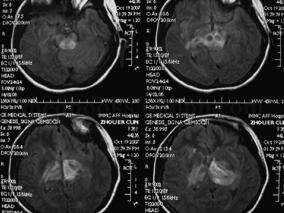

1小时条评论颈椎病广泛发生于中老年,多数患者有头晕症状伴随。若将头晕首先考虑为颈椎病,则容易掩盖小脑肿瘤等实质性疾病。小脑髓母细胞瘤是好发于儿童的小脑恶性肿瘤,成人少见,仅占颅内肿瘤的1%。笔者报道1例临床表现类似颈椎病的成人髓母细胞瘤。 临床资料 患者女性,44...